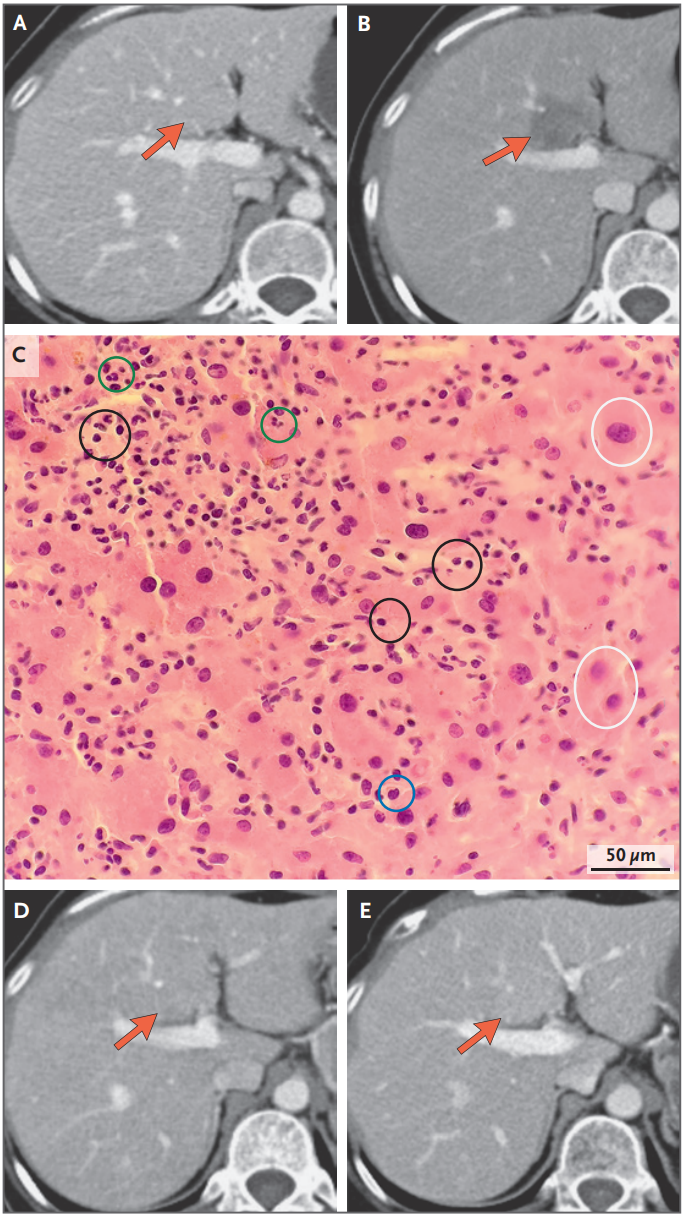

2026 年 4 月 16 日,国际顶尖医学期刊《新英格兰医学杂志》(NEJM)刊登了一篇来自宜宾市第二人民医院汪善兵团队题为:Hepatic Pseudoprogression after Treatment with Nectin-4–Targeted Antibody–Drug Conjugate 的通讯文章,报道了一位 49 岁宫颈癌患者在接受了新型抗癌药抗体药物偶联物(ADC)治疗后,肝脏出现了一个看似肿瘤进展的病灶,但最终被证实是药物起效的特殊表现。

该患者试验入组前影像学检查未见肝脏肿瘤。在治疗过程中,CT 发现肝脏病变,但肿瘤标记物明显下降,最终活检证实该病例为假性进展。这个案例不仅罕见,更对癌症治疗中的影像学评估提出了重要警示——影像学上的“进展”不一定代表治疗失败,有时恰恰是免疫系统被激活、治疗起效的信号,因此,面对复杂的治疗反应时,需要综合影像学、生物标志物和病理学证据,做出最有利于患者的决策。

治疗前的基础影像学检查显示,患者有肺部、纵隔和会阴部转移,但肝脏完全正常,没有任何可见病灶。

经过两个周期的治疗后,2023 年 7 月的复查 CT 扫描显示了一个令人困惑的现象:患者原有的转移病灶明显缩小,这通常是治疗有效的标志。

但与此同时,肝脏第四段却出现了一个新的低密度病灶,大小约为 1.8×2.5 厘米。

临床医生注意到一个重要的矛盾信号:虽然影像学显示肝脏出现新病灶,但患者的肿瘤标志物——血清鳞状细胞癌抗原却从 37.0 ng/mL 急剧下降至 1.2 ng/mL,远低于正常值上限。且患者没有发热,肝功能指标也完全正常。更令人惊讶的是,这个肝脏病灶在自发开始缩小。

为了明确诊断,医生进行了肝脏穿刺活检。病理结果显示:病灶区域有密集的淋巴细胞、浆细胞和中性粒细胞浸润,但完全没有发现恶性肿瘤细胞。

在 Nectin-4 靶向的 ADC 治疗期间出现的肝假性进展

随着治疗继续,该患者的肝脏病灶在两个月后明显缩小,到 2025 年 10 月的长期随访时已完全消退,且超过两年没有复发迹象。这位患者最终因为原有的脑转移病灶进展而退出了临床试验,但肝假性进展的发现,为医学界提供了宝贵经验——当影像学表现与生物标志物反应不一致时,不应轻易判定治疗失败,而是需要考虑假性进展的可能性,必要时进行病理学验证,避免过早停止可能有效的治疗方案。